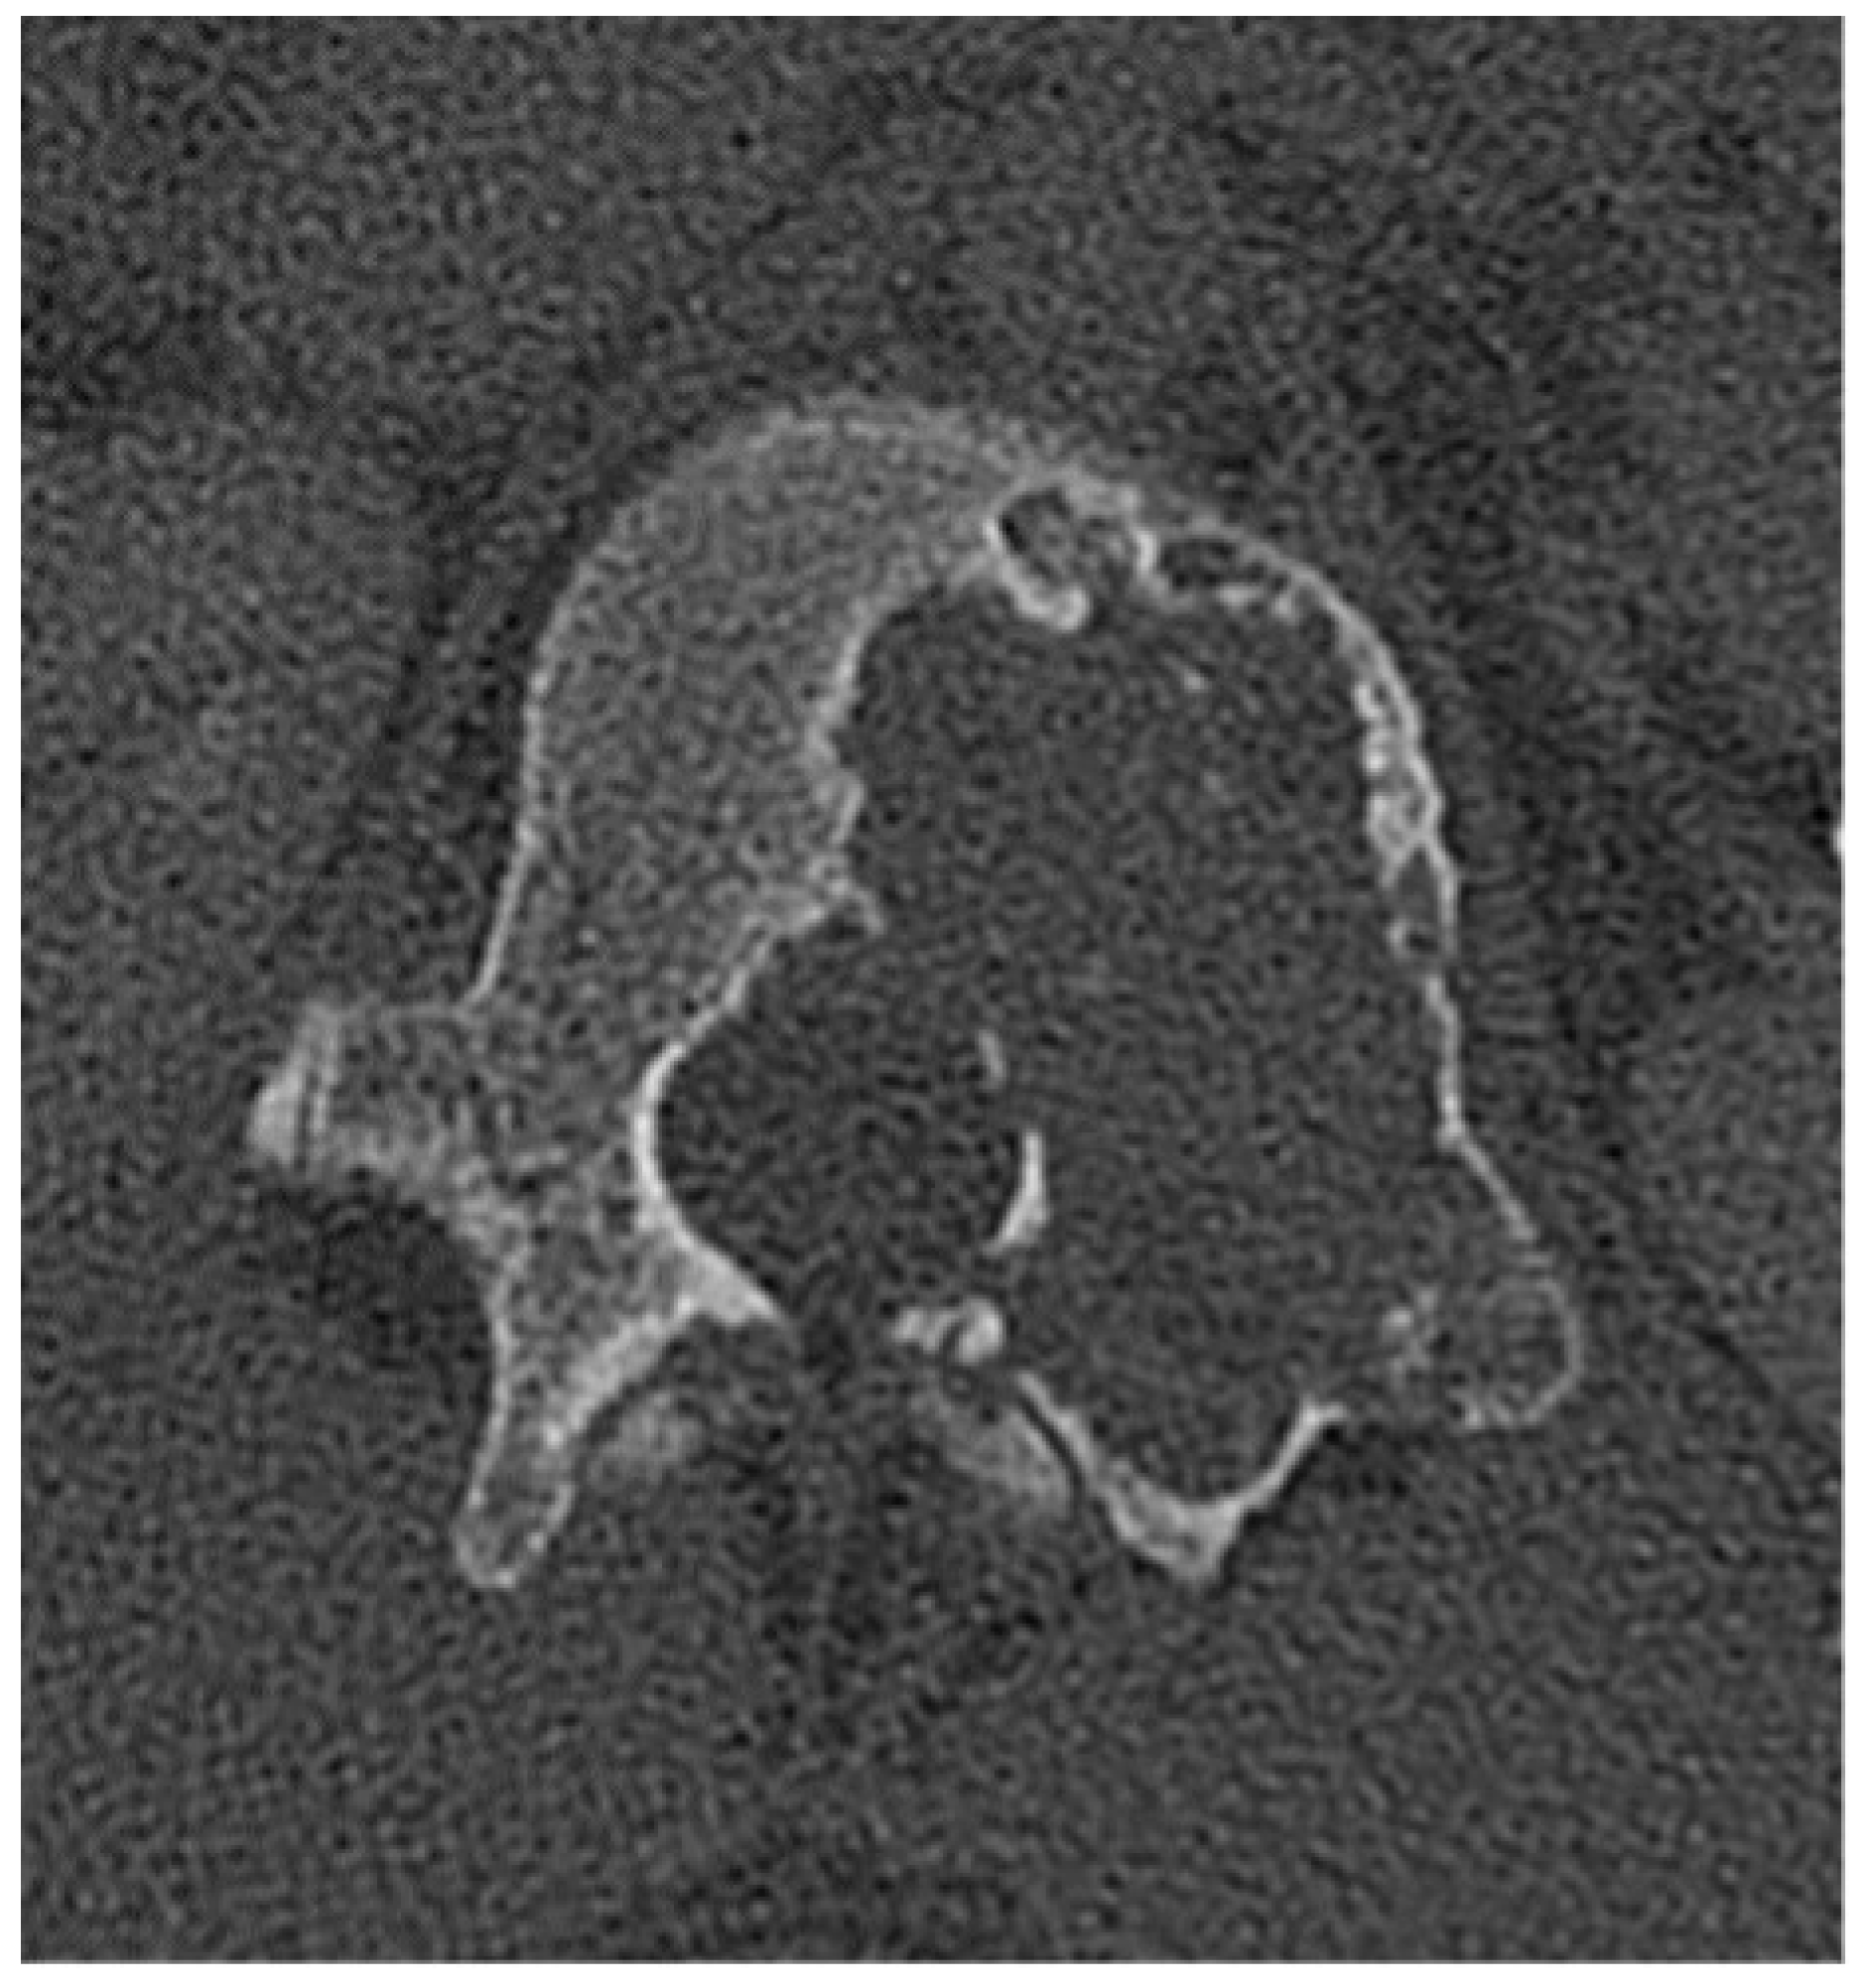

2.2.1. Osteochondroma

2.2.2. Chondroblastoma